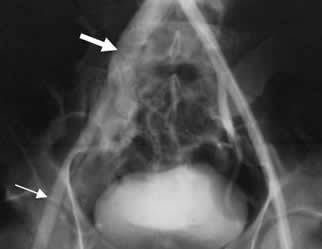

Fig 142 H. Fístula AV.

Arteriografía. Herida por arma cortopunzante en el hipogastrio. Paso tenue del contraste hacia la arteria iliaca externa derecha. (Flecha delgada). Llenado precoz de la vena iliaca común derecha, por fístula AV a nivel de la bifurcación iliaca. (Flecha gruesa).